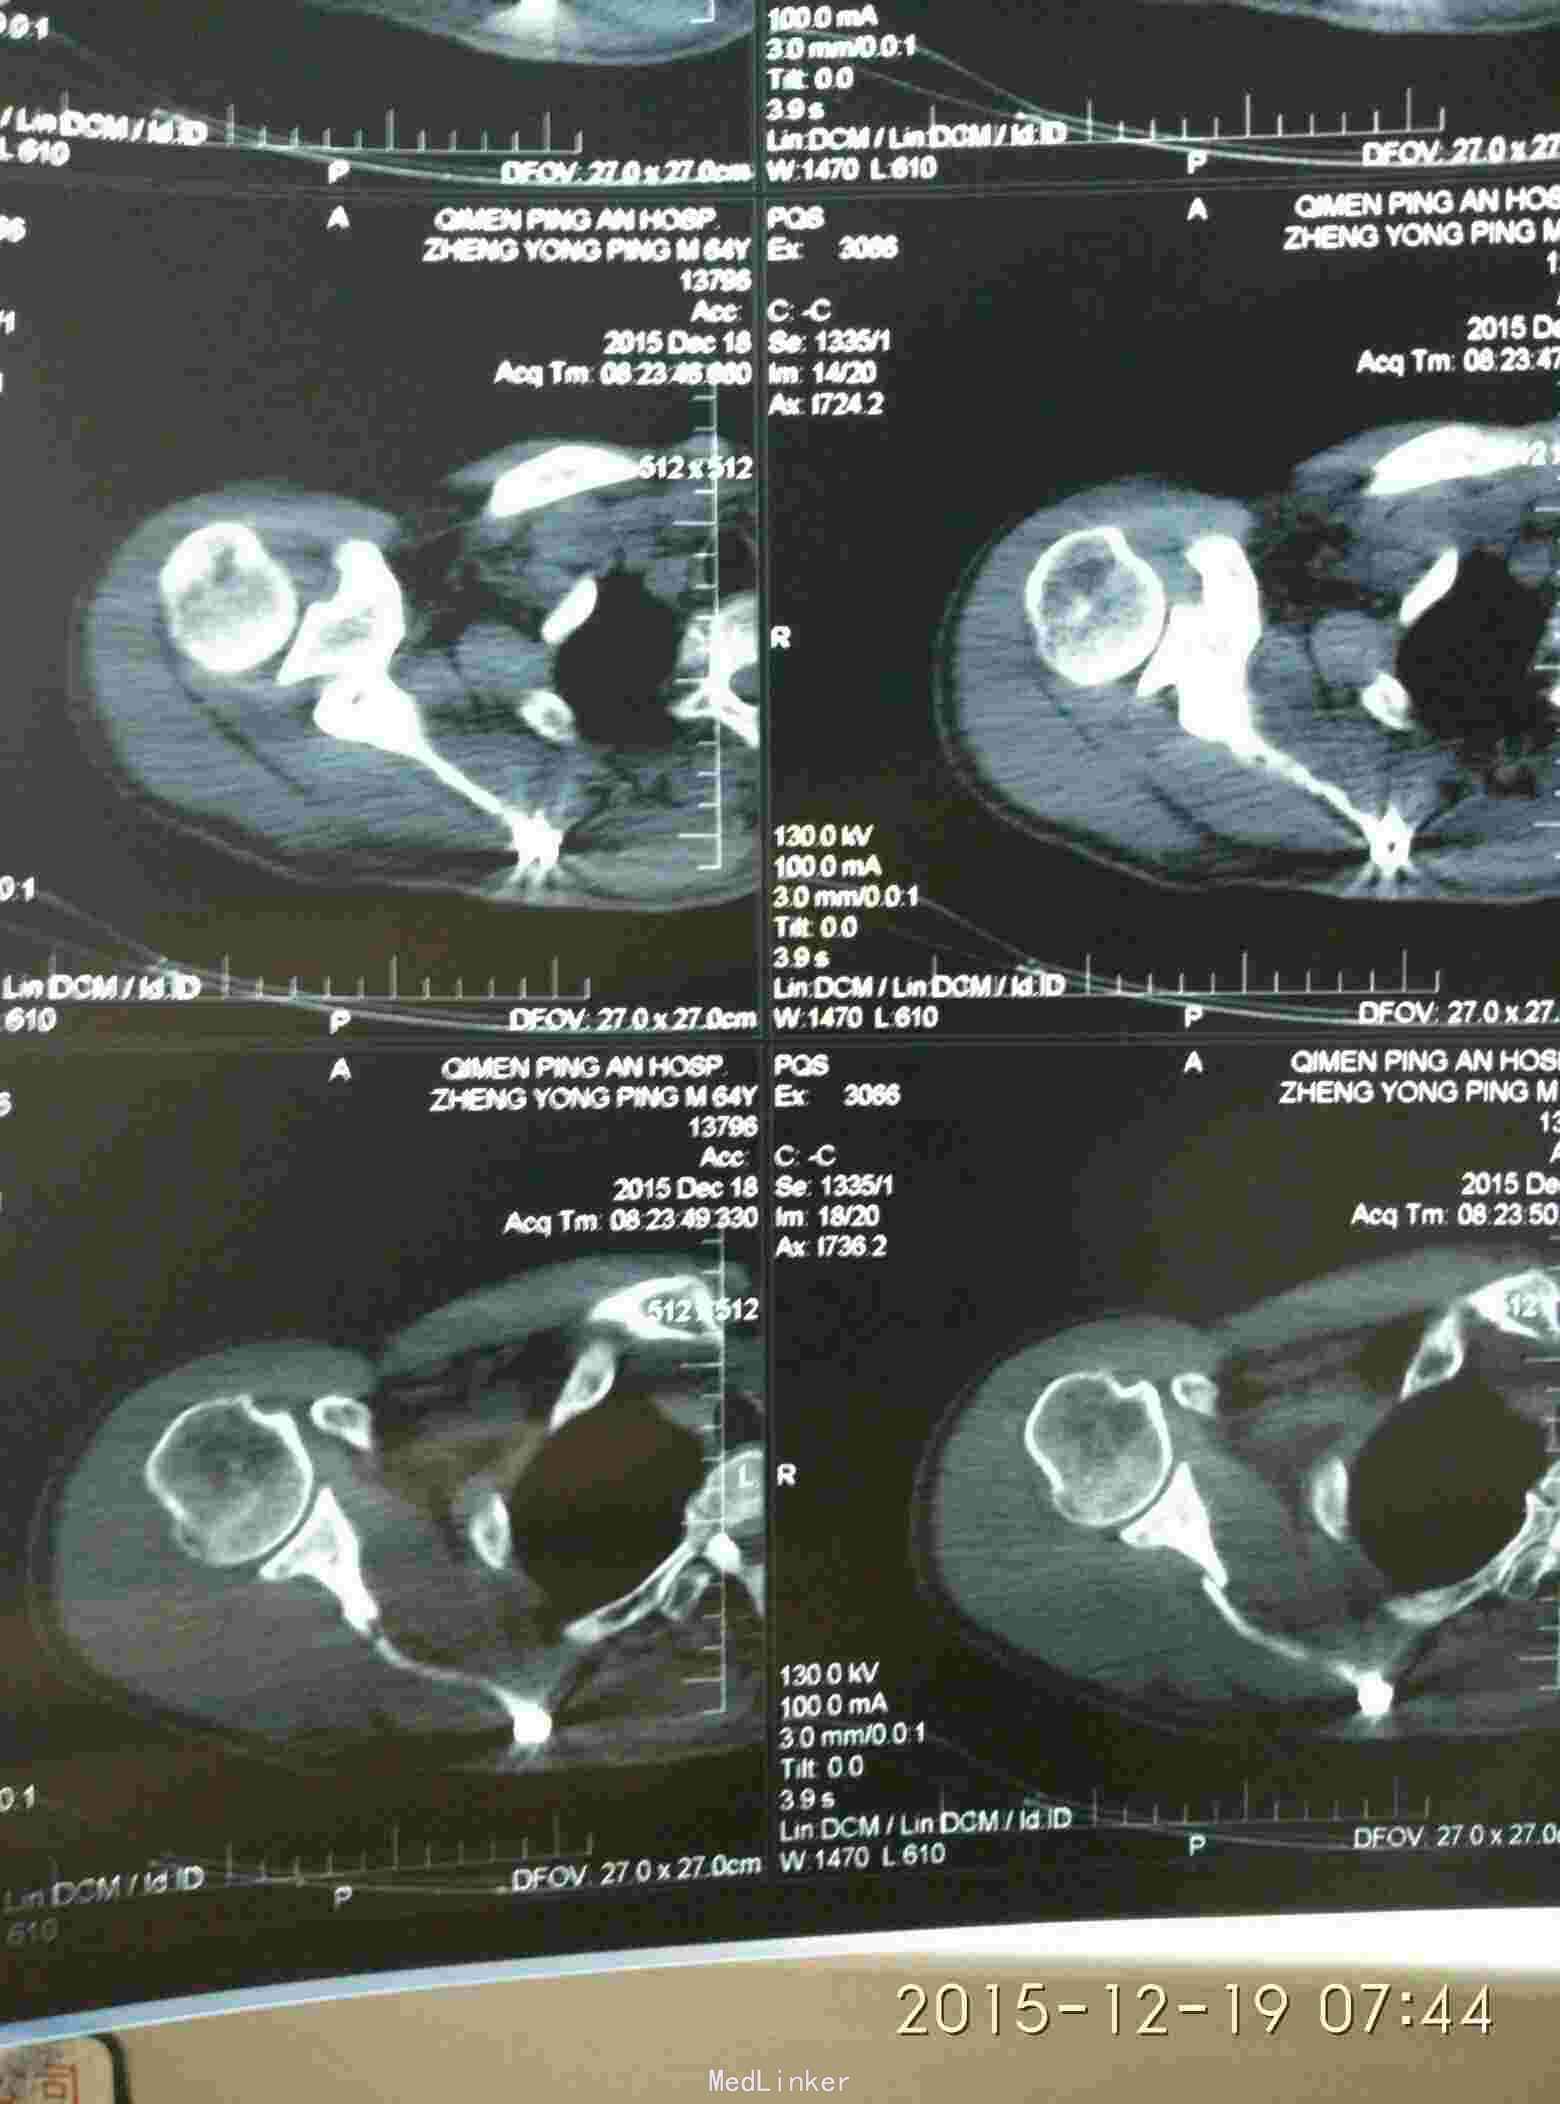

胸廓挤压试验阳性,右肩峰压痛阳性,右肩主动活动受限,外展约30度。x片及CT示右肩峰骨折及肩胛骨骨折,右第6.7.8.9肋骨骨折。

右肩峰骨折,右肩胛骨骨折,右第6.7.8.9肋骨骨折